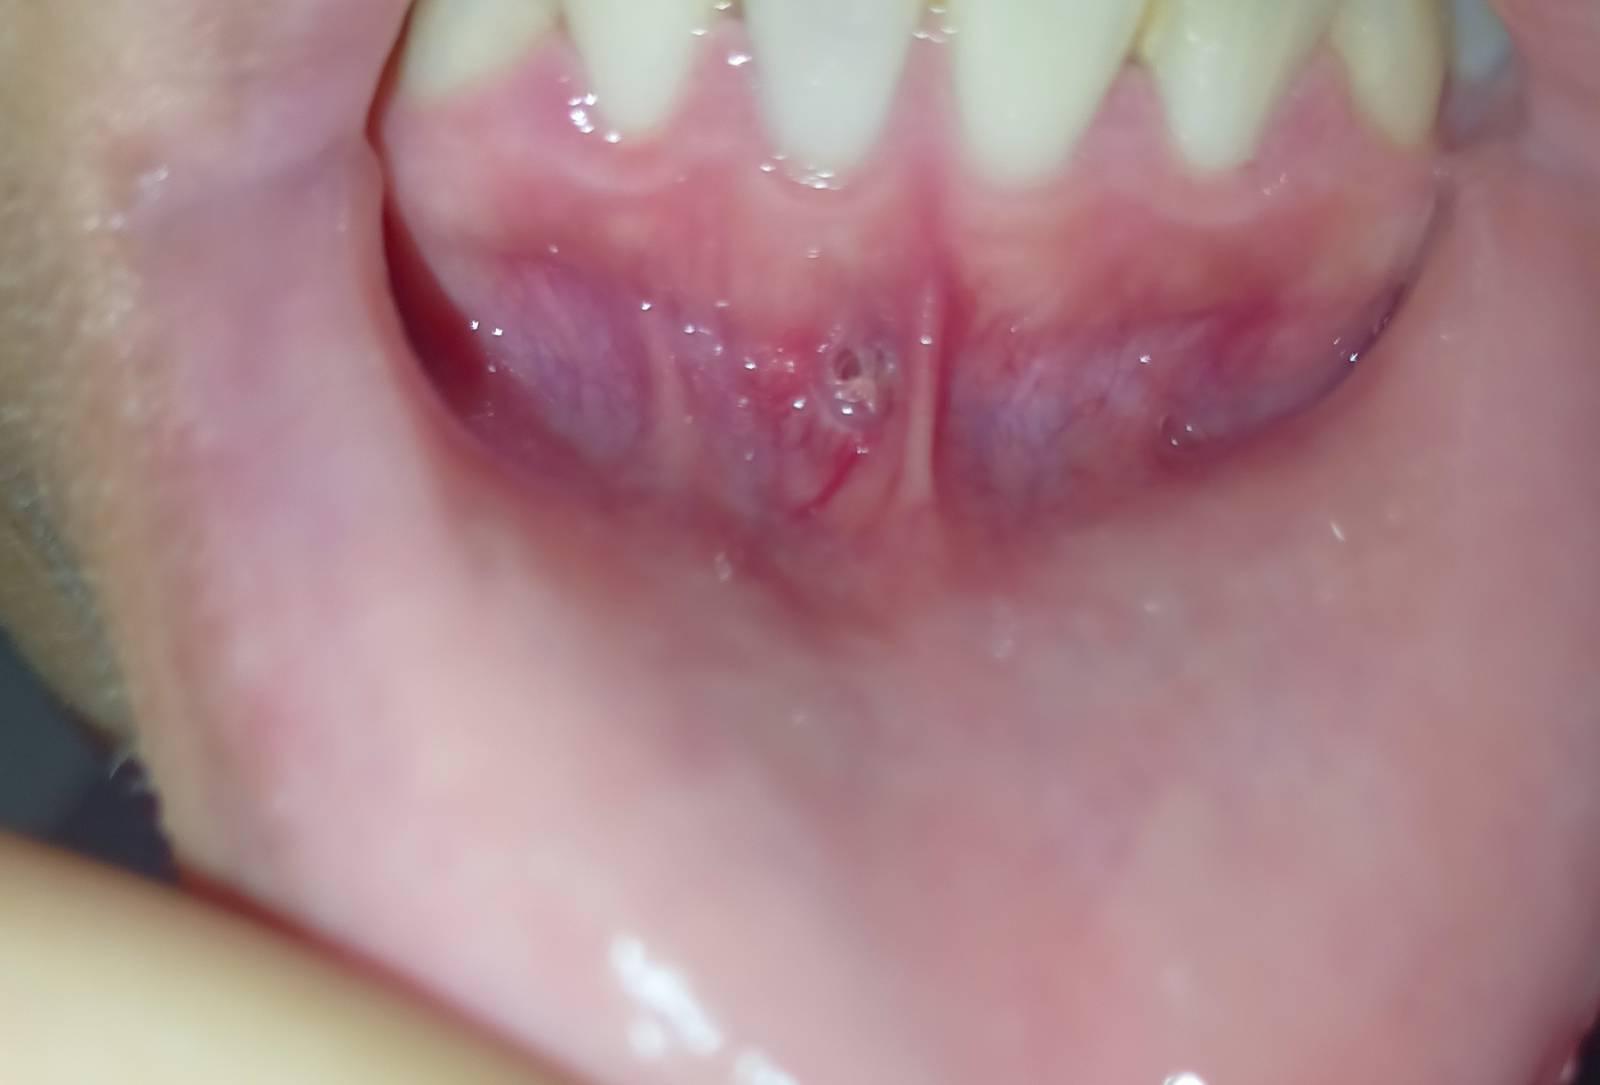

มีแผลที่เหงือกแบบนี้ คืออะไรคะ ช่วยดูหน่อยค่ะ